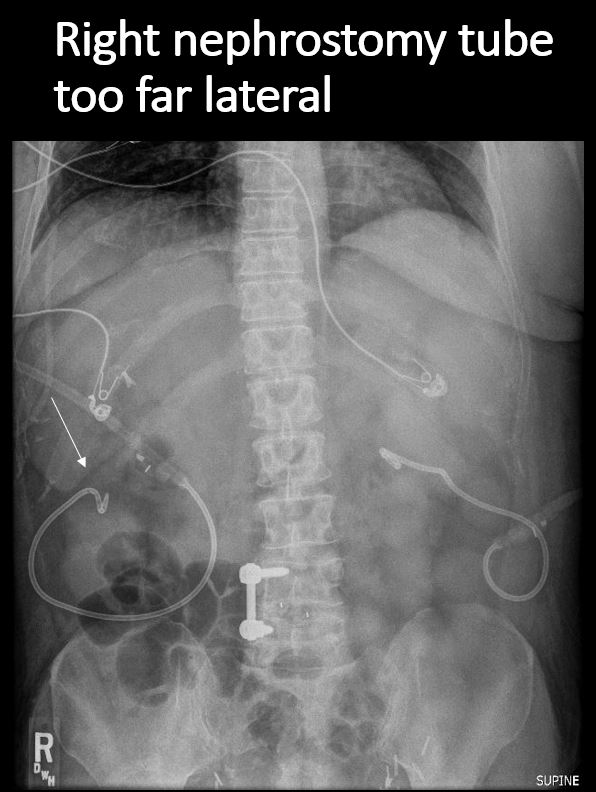

There is/are nephrostomy tubes, ureteral catheters, or a Foley catheter in place, and properly positioned. |

No | NA |